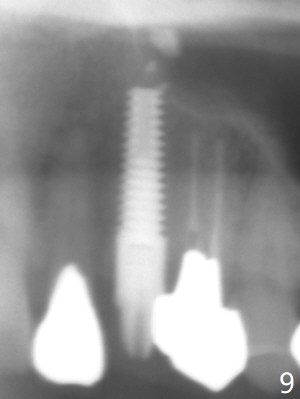

Extraction of the residual root at #11 (Fig.1) turns out to be difficult (Fig.2 (arrow: after use of small elevator). The tooth is sectioned (Fig.2 *); the palatal portion is removed, while the buccal one is trimmed until new moon-shaped and subgingival (Fig.3 * (gauze (G) packed in the socket while photo taking)). Initial osteotomy is 20 mm deep with nasal floor perforation (Fig.4). The subsequent depth is 17 mm (Fig.5). When a 5x17 mm tissue-level implant is placed (Fig.6,7; >60 Ncm), there is a gap between it and the socket shield (Fig.6 *). Gap-filling Vera Graft (Fig.8 *) also covers the shield prior to fabrication of an immediate provisional (Fig.9). There is no apparent bone loss 3.5 months postop (Fig.10). There is no buccal plate resorption 9 months postop (Fig.11). The implant is doing well 2 years postop (1 year 9 months post cementation, Fig.12).